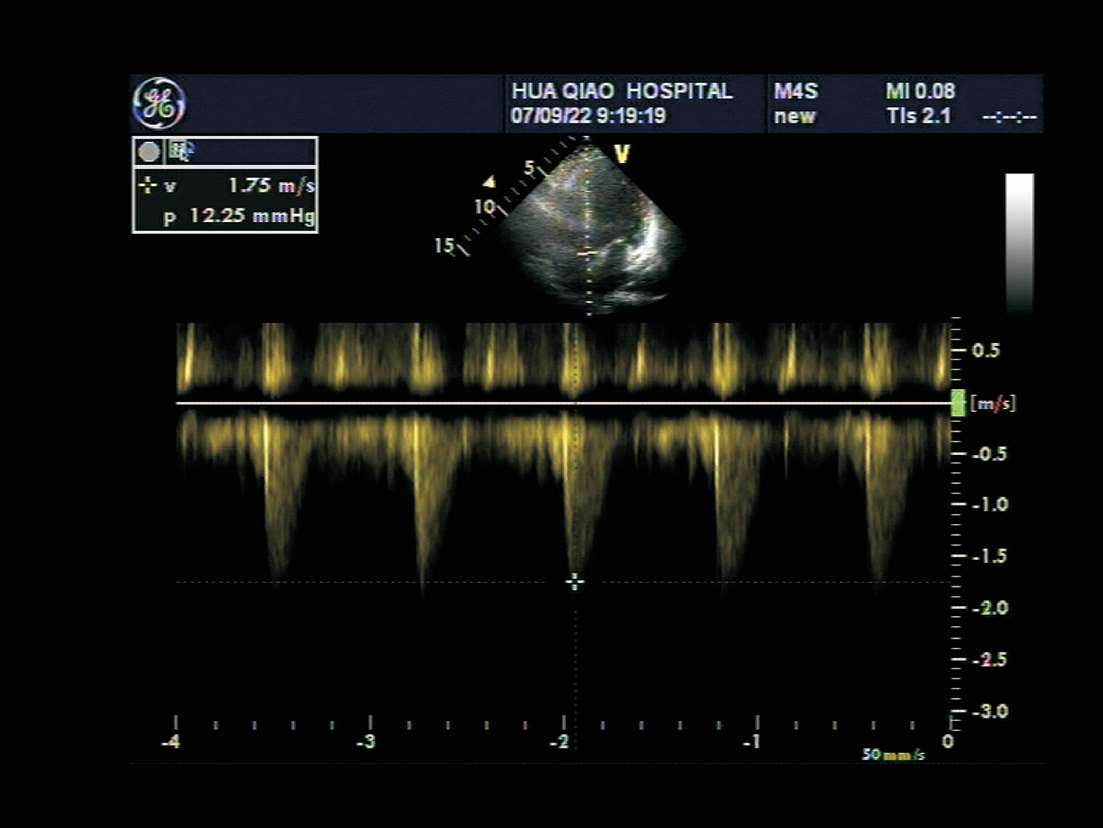

主动脉瓣口脉冲型频谱多普勒取样框置于主动脉瓣口水平,取样线平行于血流。收缩期可见一向下空心三角形窄带频谱(见图1-35)。

图1-35 主动脉瓣口脉冲型频谱多普勒